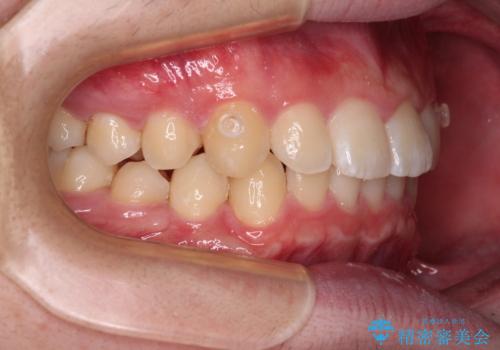

【モニター】斜めに突き出した前歯をインビザラインで改善

- 前方に傾斜した前歯を気にして来院された患者様です。

強く食いしばってしまう癖があり、下顎前歯に押し出されて上顎前歯が前方へ斜めに突き出している状態でした。

IPR(歯と歯の間を削る)を多用して、インビザラインにて矯正治療を行うこととしました。

口元を引っ込めるためのゴムかけを頑張っていただき、満足のいく上顎前歯の傾斜へ改善することができました。